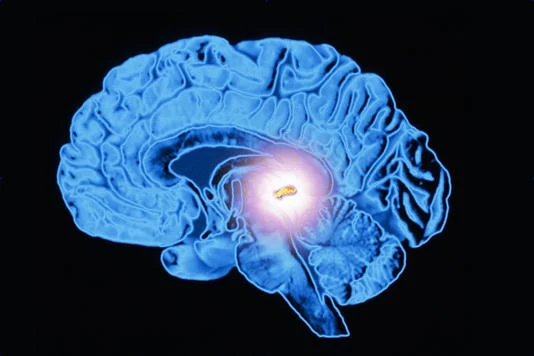

قصور الغدة الصنوبرية هو حالة طبية نادرة تحدث عند وجود خلل في وظيفة الغدة الصنوبرية (بالإنجليزية: Pineal Gland)، وهي غدة صغيرة جداً لا يتعدى حجمها حجم حبة البازلاء، تقع في عمق المخ بين الفصين الأيمن والأيسر، وقد احتل التعرف على أسباب قصور الغدة الصنوبرية مساحة كبيرة من البحث والدراسات العلمية في الآونة الأخيرة؛ نظراً لأن الغدة الصنوبرية هي آخر أجزاء المخ التي تم اكتشافها حتى الآن.

تعد الوظيفة الأساسية للغدة الصنوبرية هي إفراز هرمون الميلاتونين الذي تنتجه الخلايا الصنوبرية، وهو الهرمون المسؤول عن تنظيم الساعة البيولوجية للجسم، كما أثبتت الأبحاث وجود علاقة بين الغدة الصنوبرية وبعض الوظائف الحيوية المتعلقة بصحة القلب والعظام.